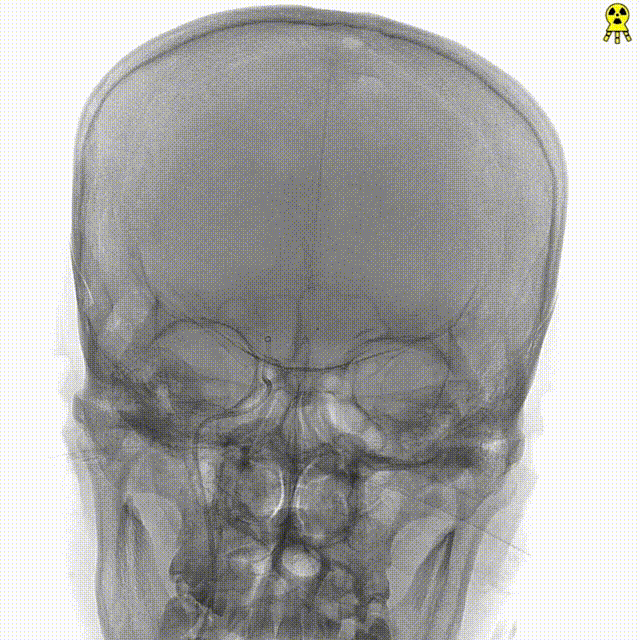

右侧颈内正位造影

右侧颈内侧位造影